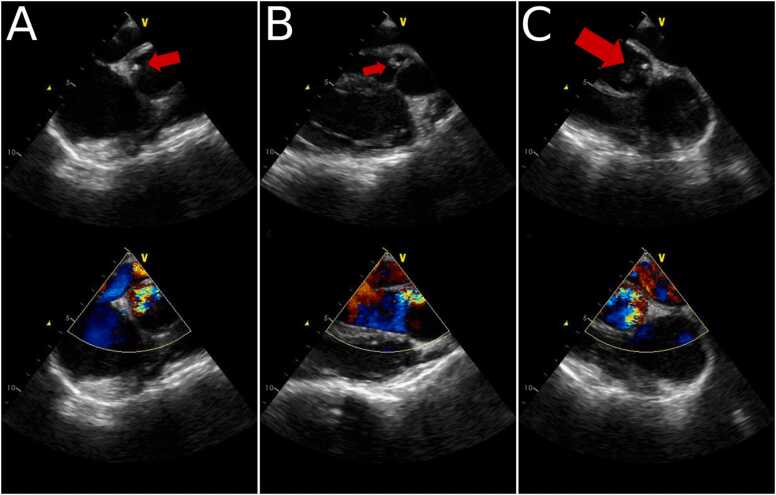

All of the subsequent blood cultures were negative for bacterial growth. Cerebral arteriography showed left MCA bifurcation aneurysm, left M1 branch stenosis, and left M2 superior division occlusion. A follow up transthoracic echocardiogram, done 20 days after the first TTE, showed a slight decrease in the size of the vegetation 0.6 × 0.6 cm, with significant aortic regurgitation. Transesophageal echocardiogram was done at day 27 of admission. It showed the mobile echodense mass attached to the aortomitral fibrosa, of 0.4 × 0.4 cm in size, with severe aortic valve regurgitation, and a preserved ejection fraction (Fig. 2).

Fig. 2.

Transesophageal echocardiography reveals the presence of a vegetation at the aortomitral fibrosa (arrows) with aortic valve regurgitation.